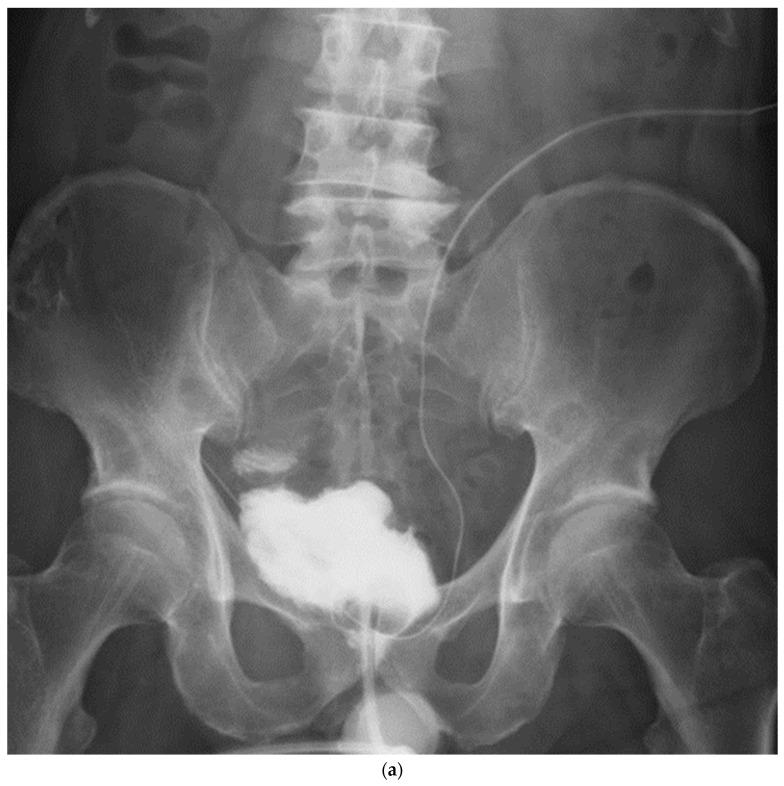

A total of 10 male patients with a median age of 66 years underwent robot-assisted radical cystectomy (RARC) with an orthotopic NB via a hybrid approach from March 2022 to February 2023. After the isolation of the bladder and bilateral pelvic lymphadenectomy, Wallace plate creation was performed, and the robot was undocked. We extracorporeally performed the removal of the specimen and a side-to-side ileoileal anastomosis, and then the VIP NB posterior plate was rotated 90 degrees counterclockwise using a 45 cm detubularized ileum. The robot was redocked; then, circumferential urethra-ileal anastomosis, side-to-middle anterior wall closure, and ureteric afferent limb anastomosis were performed.

The NB configuration using the modified VIP method for a hybrid approach is a feasible surgical technique to minimize the movement of robotic forceps. In particular, it may be more useful in Asian individuals with narrow pelvises.